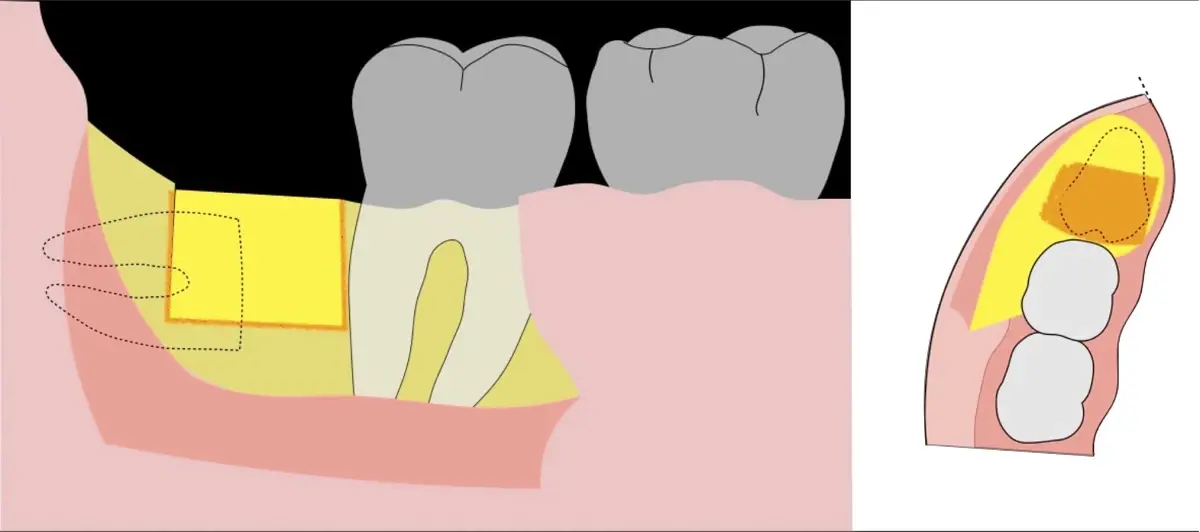

En contraste, el instrumento piezoeléctrico utiliza un corte micrométrico que retira un área de superficie mínima de hueso, y reduce el riesgo de termonecrosis marginal en comparación con las fresas rotatorias convencionales.9 Los micromovimientos mejoran la precisión en el corte y el control táctil, y eliminan las macrovibraciones que se producen con los instrumentos rotatorios.10 Su frecuencia de oscilación es la amplitud de 60-200 μm horizontalmente y de 20-60 μm en sentido vertical, lo que es muy inferior en comparación con las micro sierras oscilantes; por lo tanto, proporciona cortes de osteotomía precisos y seguros. Adicionalmente, posee vibraciones ultrasónicas que descomponen el líquido de irrigación en partículas muy pequeñas (fenómeno de cavitación, que produce un efecto hemostático y así reduce la pérdida de sangre), lo que proporciona una visión clara y sin obstáculos del campo quirúrgico11,12.

El procedimiento se inicia colocando anestesia troncular para bloqueo del nervio dentario inferior y sus ramas. Luego, se establecerá el diseño de acceso según la disposición de la molar a extraer. Para fines didácticos, se explicará cómo se realizaría la extracción de la molar de la Figura 1: se realiza una incisión horizontal a nivel de la zona retromolar hasta llegar a distal de la segunda molar, continuándose con una incisión intrasurcular hasta mesial de la segunda molar, finalizando con una incisión vertical a espesor total hasta llegar a la línea mucogingival (Figura 2).